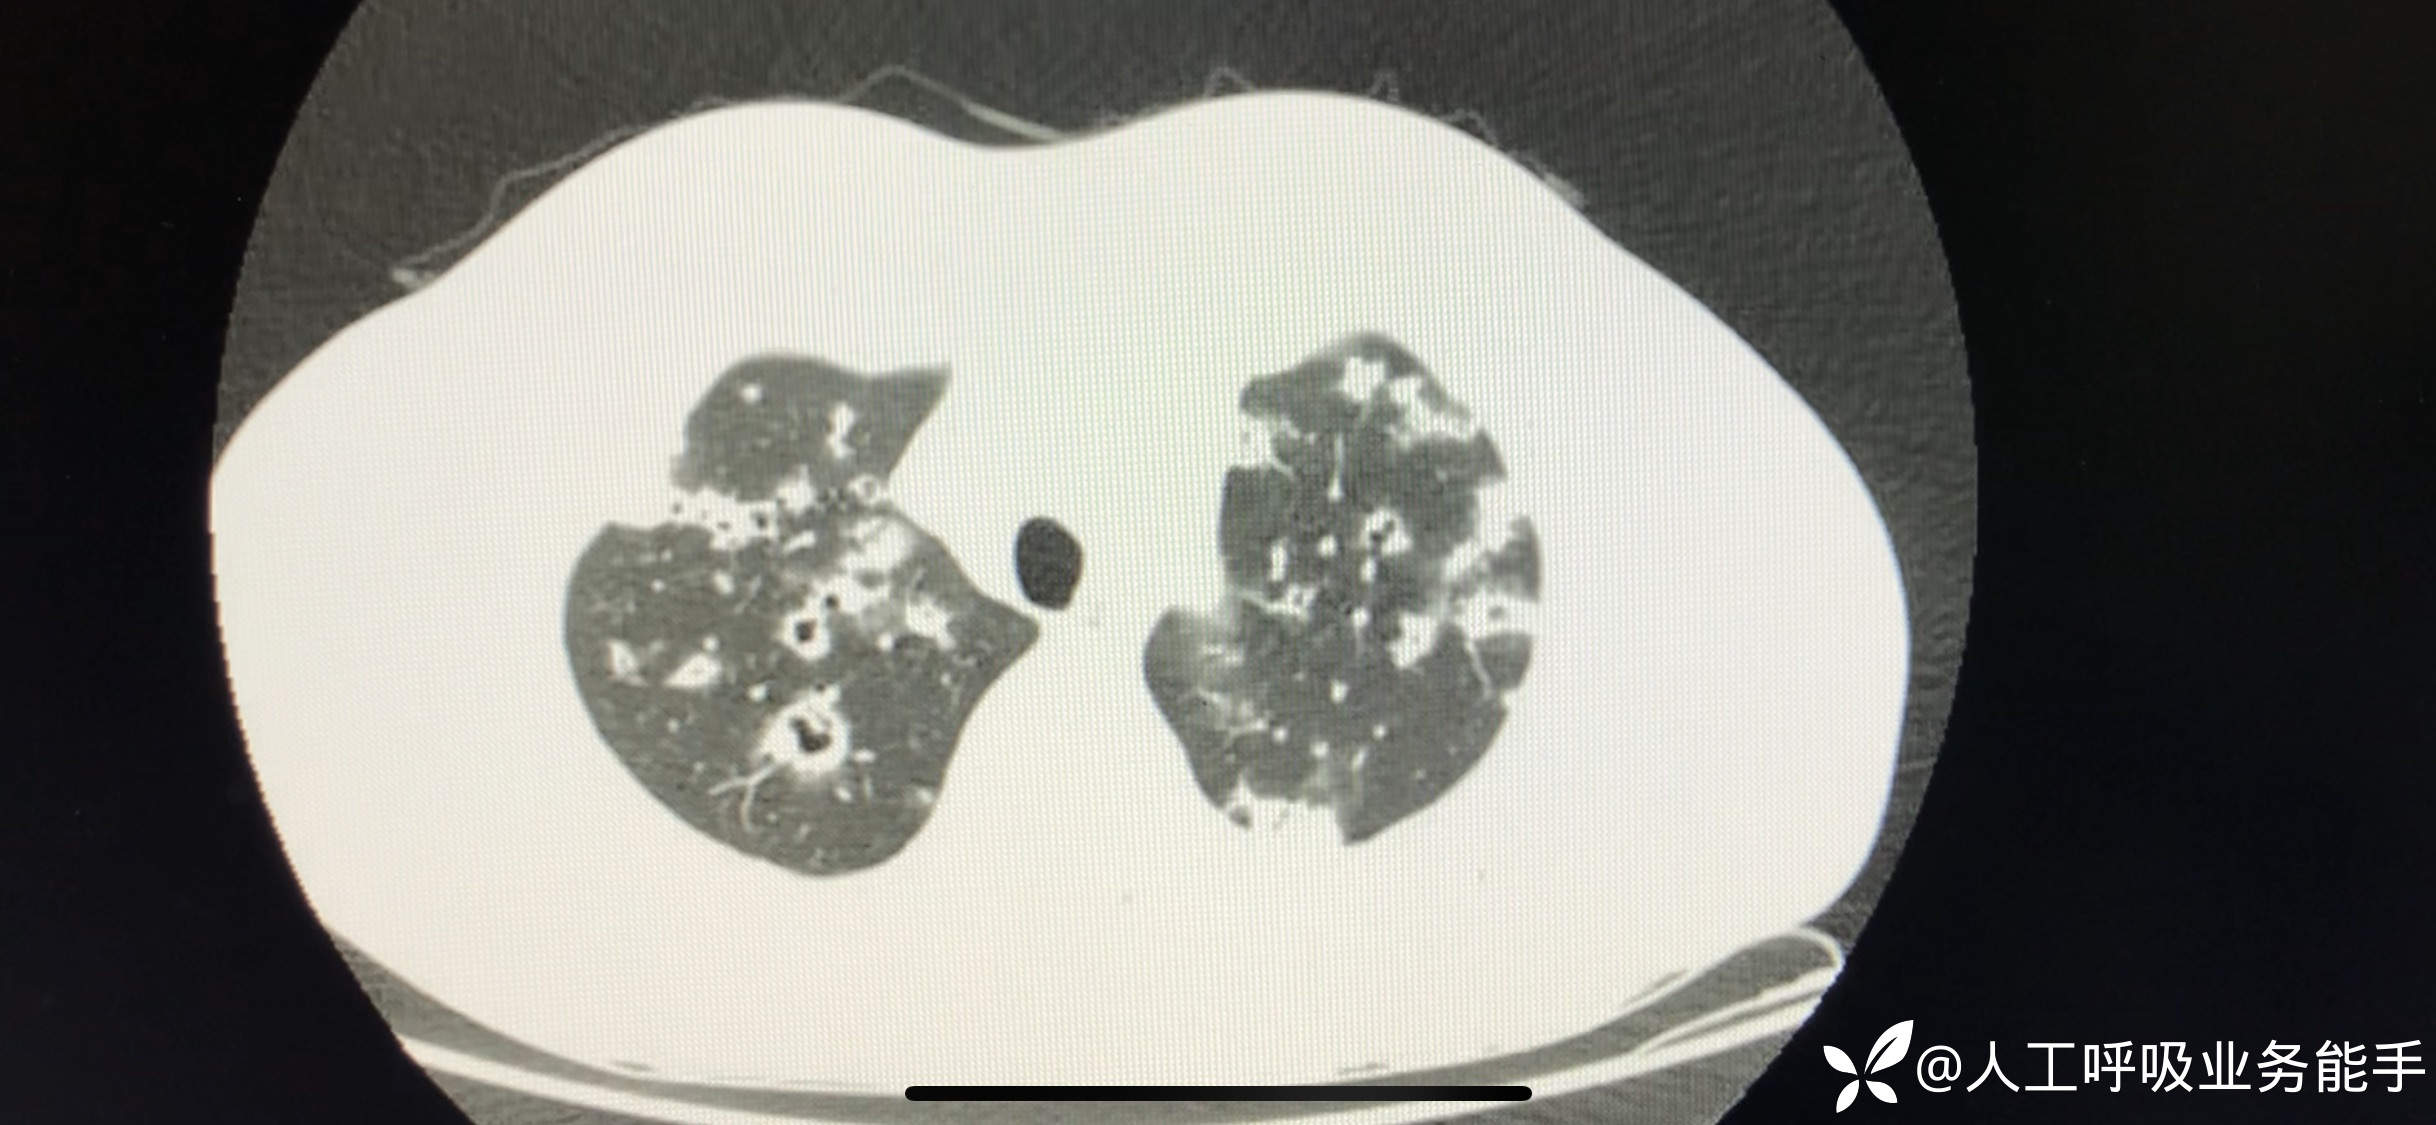

初诊影像: